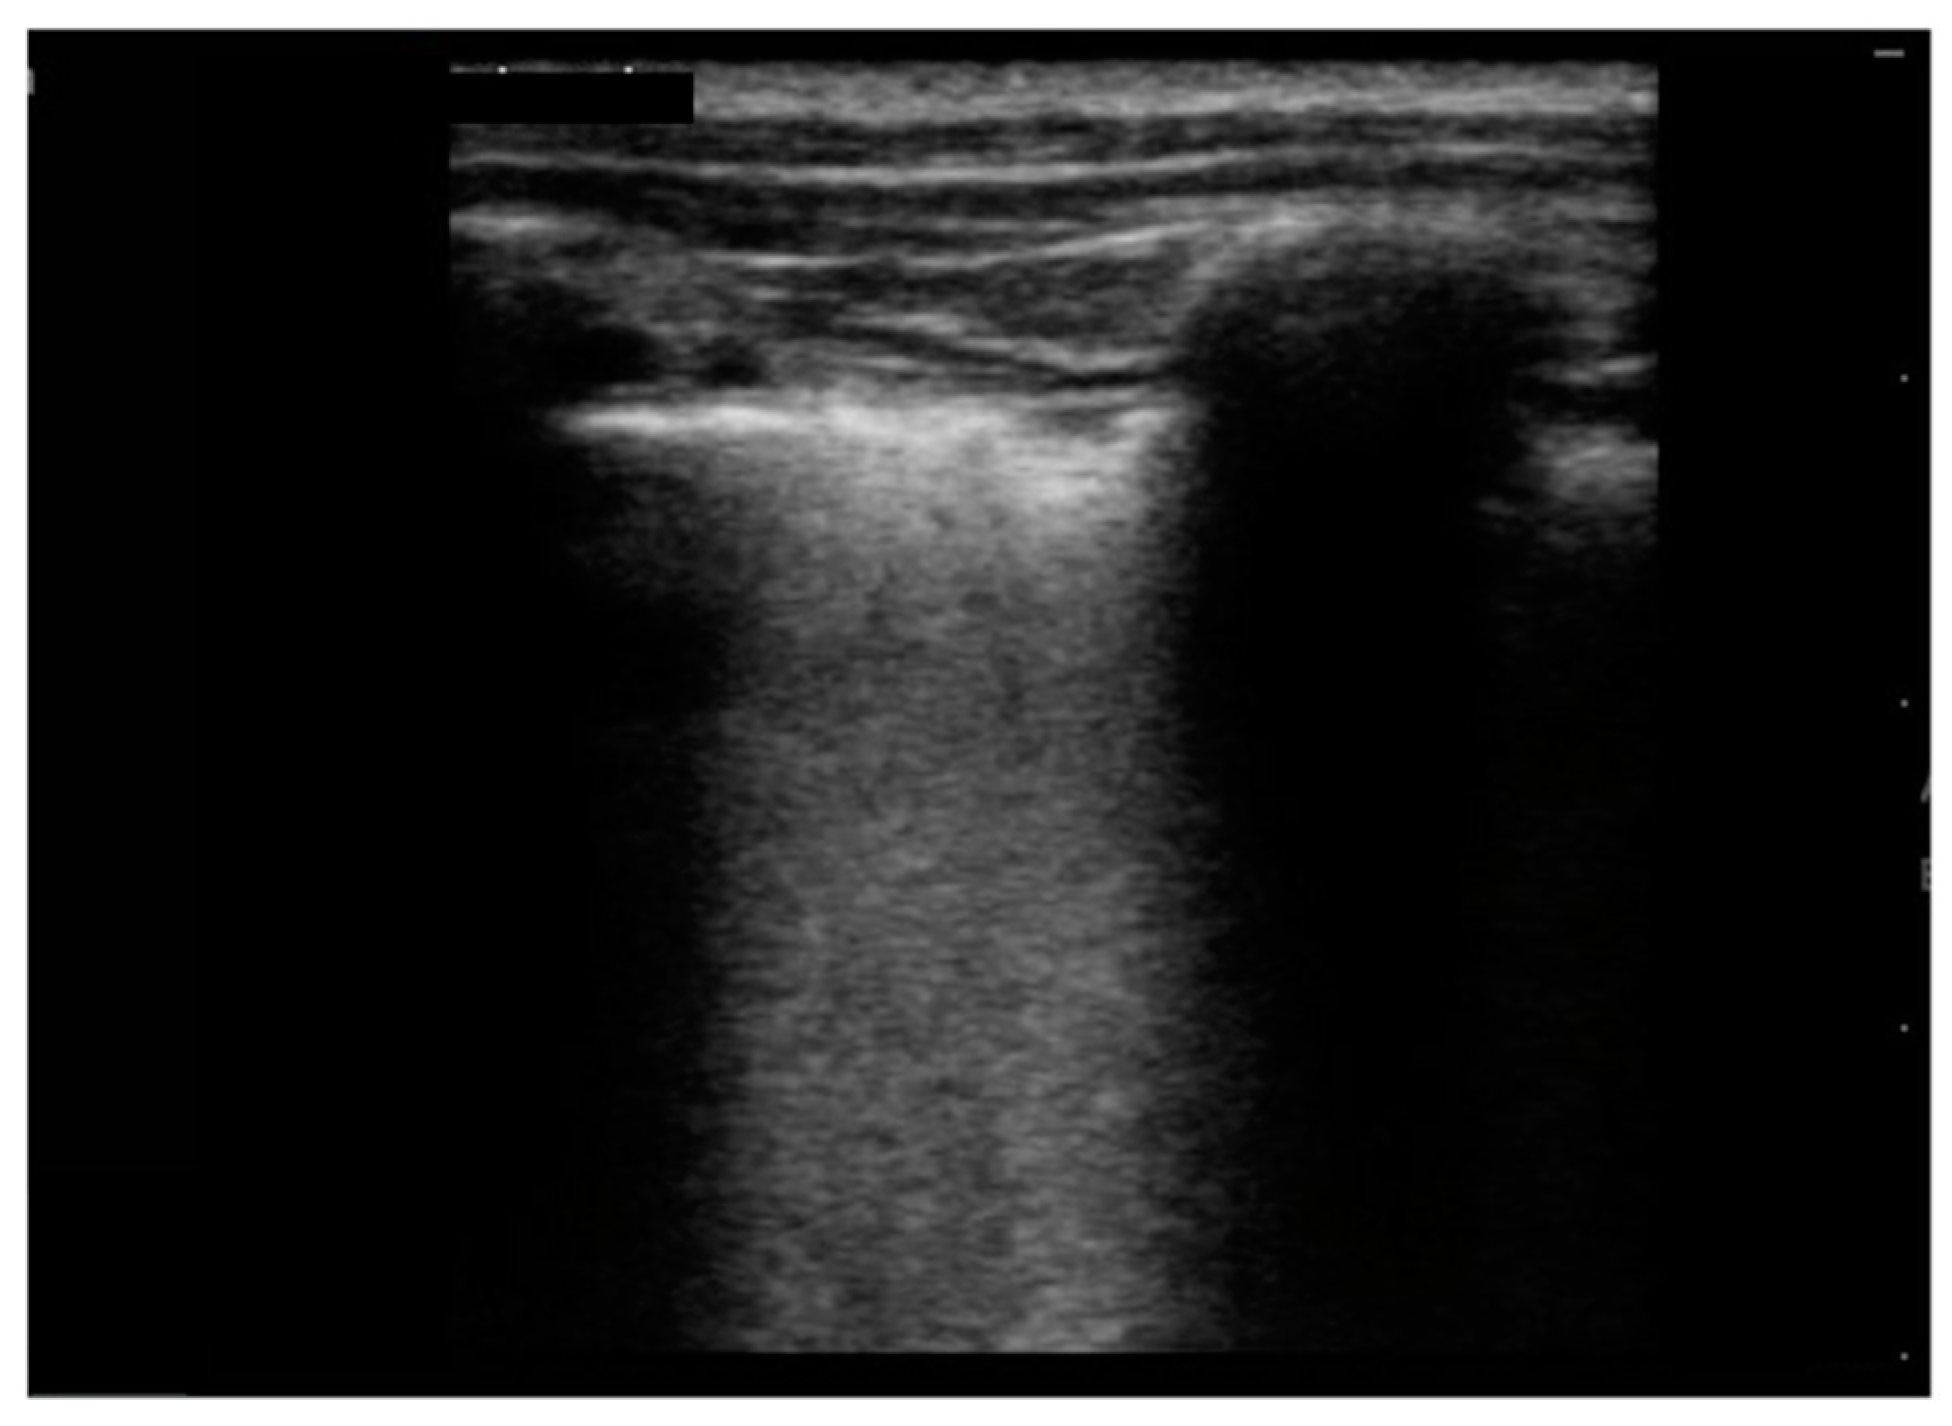

| Irregular/indented/broken pleural line, n (%) | 10 (100) | |

| B-lines, n (%) | 10 (100) | |

| Multiple/several B-lines, n (%) | 8 (80) | |

| White lung, n (%) | 5 (50) | |

| Sub-pleural consolidation, n (%) | 7 (70) | |

| Pleural effusion, n (%) | 9 (90) | |

| LUS score, mean ± SD | 10.5± 1.81 |